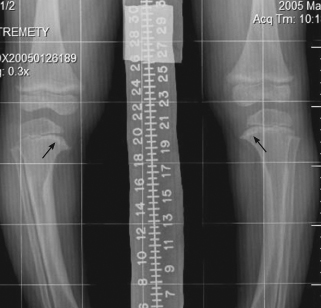

An anteroposterior view of both knees with weight bearing is shown.

The radiograph shows bilateral genu varum deformity, with bowing and beaking of the medial metaphysis of the tibia. Reactive cortical thickening in the medial aspect of the tibial shaft is present bilaterally. These findings are suggestive of Blount disease.

Radiographs are helpful in making the diagnosis. An anteroposterior standing radiograph of both extremities and lateral radiograph of the affected extremity are typically obtained. The findings include sloping and fragmentation of the medial epiphyseal ossification center, widening of the growth plate, and “beaking” of the medial metaphysis, as seen in this case. MRI is often helpful in evaluating the growth plate in adolescent Blount disease.